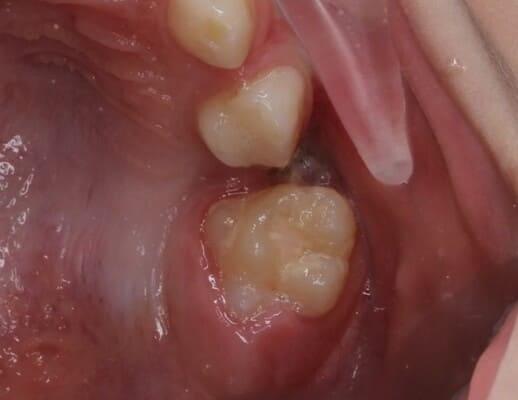

Дівчинка 2 років, але зуби вже мають глибокі ураження із залученням у запальний процес пульпи (“нерва”) зуба. На жаль, так трапляється і зволікати в такому випадку не можна. Було проведено лікування в умовах анестезіологічного забезпечення під контролем досвідченої анестезіологічної команди. Передні зубчики відновлено естетичними коронками, на жувальних зубчиках проведена герметизація фісур, а один вже має глибоке ураження карієсом, тому теж покритий коронкою. Одразу після лікування ясна можуть виглядати дещо травмованими, але за кілька днів вони повністю відновляться.